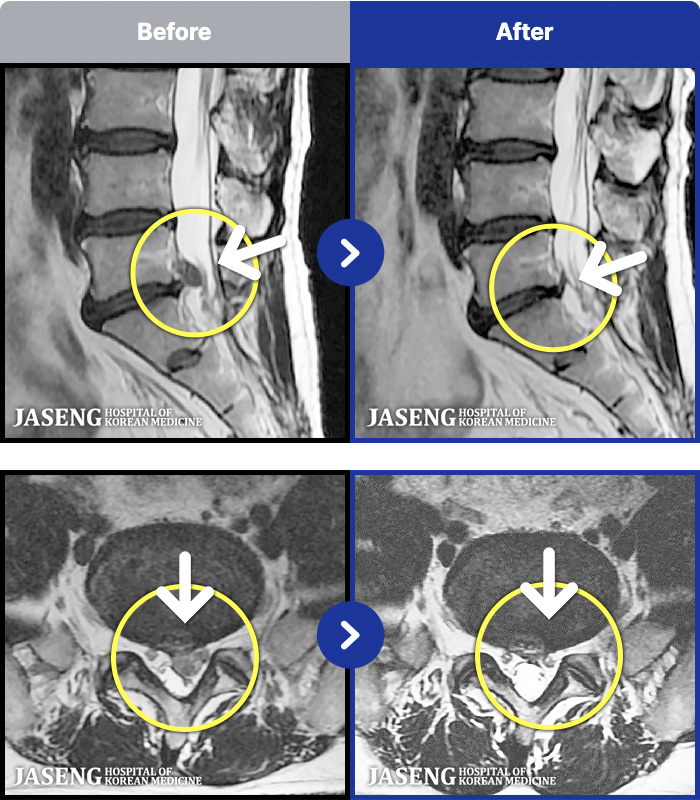

1,237 MRI ũ ʸ Ȯϼ.

㸮 ϻ .